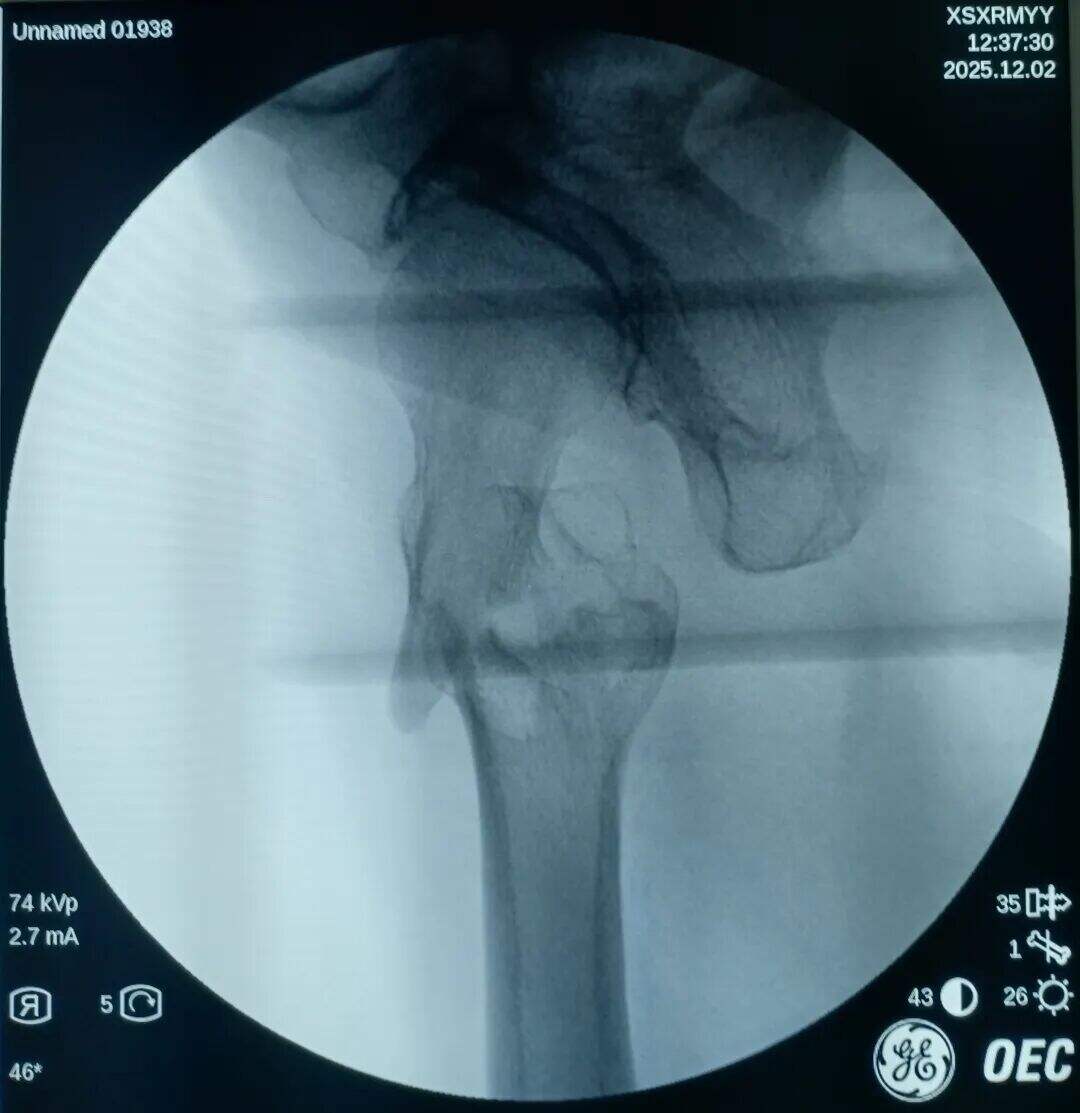

Narezen je bil 2 cm prednji mini-rez. Mesto zloma je bilo opazovano z prstom. Ugotovljeno je bilo, da je proksimalni fragment premaknjen navzgor, distalni fragment pa nazaj in zaklenjen. V mesto zloma je bil vstavljen klešča; pod vodstvom prsta v kombinaciji s kleščo so bili zaklenjeni fragmenti odklenjeni. Nato je bila klešča uporabljena za ohranitev kakovosti redukcije z medialno in lateralno kompresijo. Izvedena je bila običajna lokalizacija, vstavitev vodilne žice ter standardni kirurški postopek.

Medularni kanal je bil ozek. Nobenega razširjanja ni bilo izvedeno. Intramedularni klin s premerom 9 mm je bil vstavljen v tesen fit. Prilagoditev anteversije cefalomedularnega vijaka se je izkazala za težko.